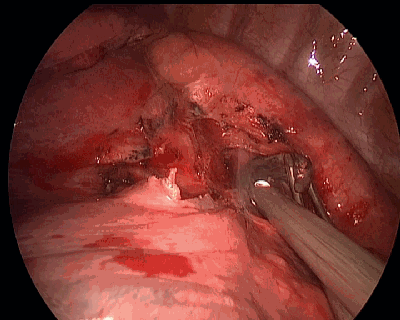

超声刀夹持住淋巴结底部的疏松组织,运用切割+张力将淋巴结移除。这一动作经常被用来清除淋巴结,包括支气管上淋巴结的剔除。

超声刀夹起淋巴结底部然后将之摘除,因为超声刀刀头温度较双极电凝止血钳温度更低,止血效果更好,所以超声刀更适合于这个动作。